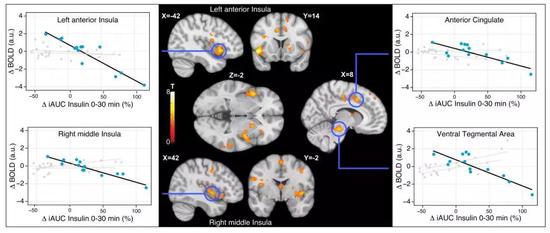

当fMRI检查志愿者大脑内相关味觉区域的耗氧量,也可以发现,代糖真糖组合令志愿者大脑对甜味的反应减弱了,对其他几种味觉的反应没有发生变化;而代糖组和蔗糖组,每种味觉都没有发生变化。

胰岛素反应与大脑对甜味的感知成反比